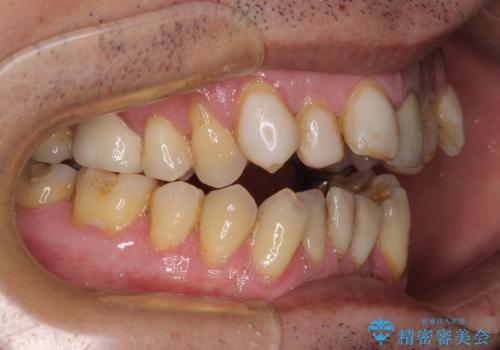

- 長年気になっていた口元を改善したいとのことで来院された患者様です。

外科手術を併用した矯正治療を検討するほどに隙間の空いた開咬と、顕著な叢生が認められました。

開咬の改善には、舌の突出癖改善のためにトレーニングを行いつつ、インビザラインでの矯正治療が大変有効ですが、上顎骨が下顎骨に対して前方位に位置しており、インビザライン単独で治療を行うよりは補助装置とワイヤー矯正で奥歯の咬み合わせを改善してから、開咬改善のためのインビザライン矯正治療を行うこととしました。

奥歯の銀歯は、土台の一部に抜歯が必要であったので、矯正治療の途中で抜歯してからオールセラミックブリッジによる補綴治療を行うこととしました。